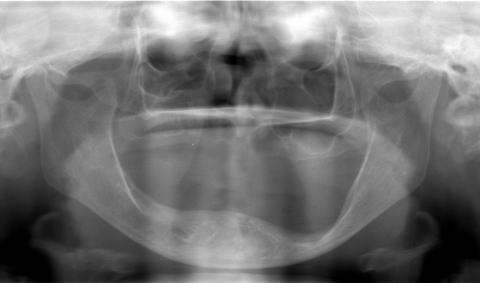

(図6)初診から33年経過(2008年1月7日)、71歳。咬耗は進んでいるが、骨植は堅固である